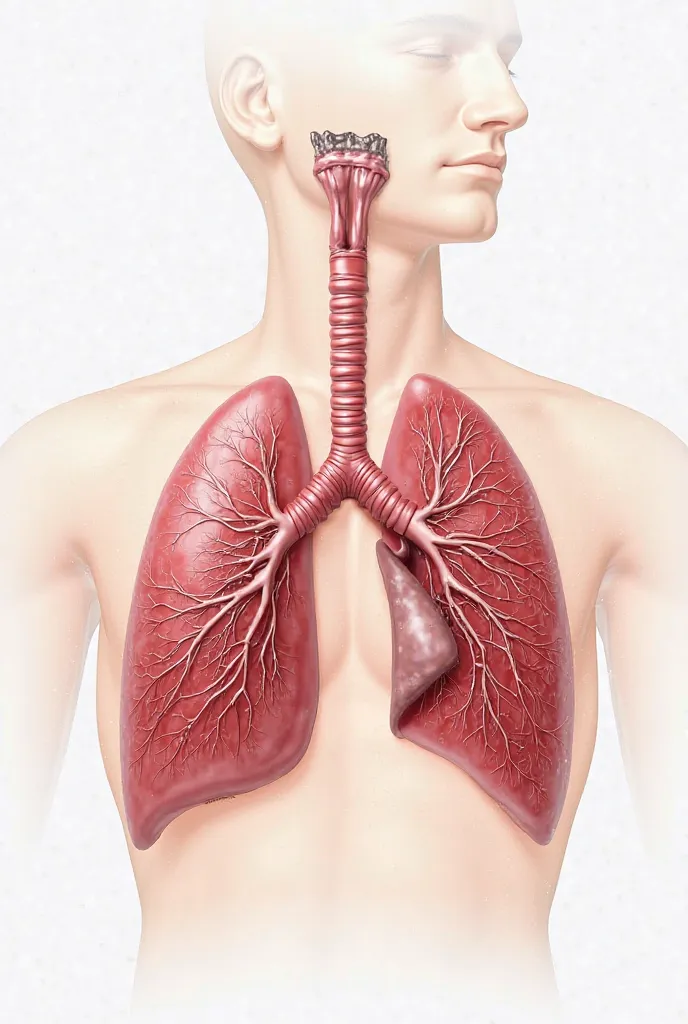

Make a folder about bacterial pneumonia

Make a folder about bacterial pneumonia

Make a folder about bacterial pneumonia